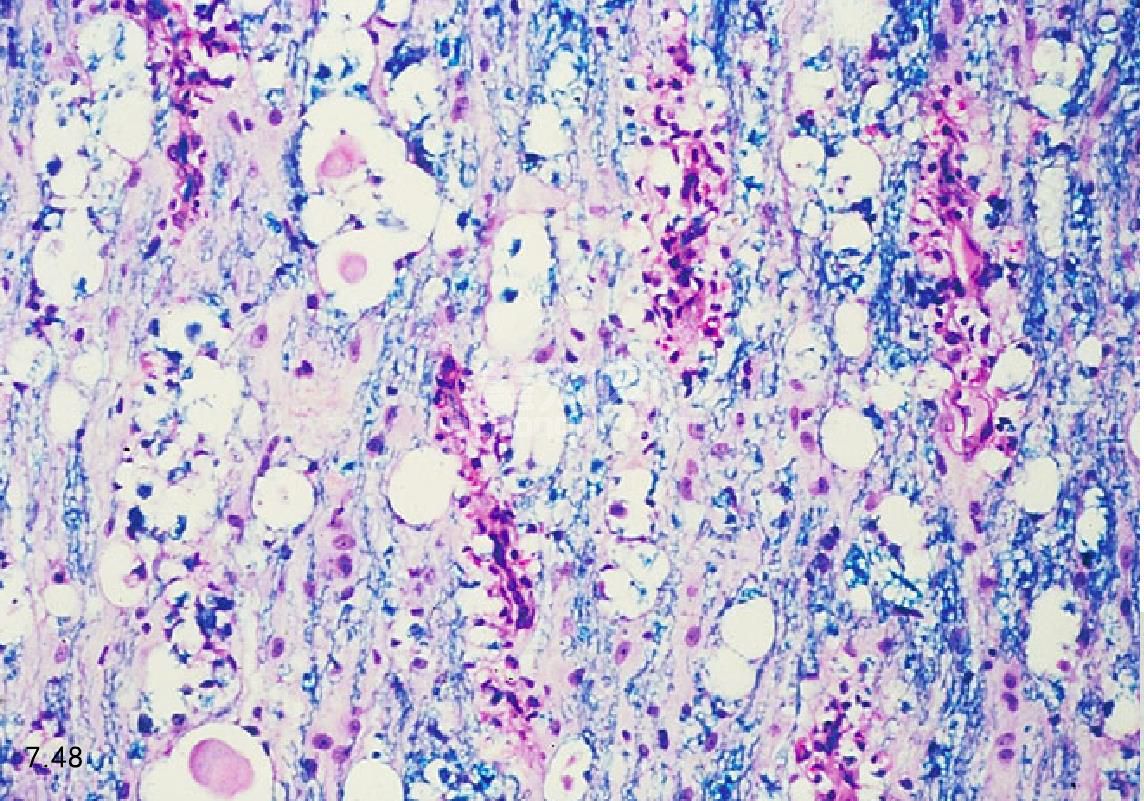

临床症状 临床症状的出现不易察觉,为缓慢的进行性疾病。起初的症状包括后肢共济失调和带有意识性固 有感觉丧失的轻瘫(图7.47和图7.48)。痛觉、前肢功能和反射正常,且少见大小便失禁。可出现后肢脊髓反射 过度,但若神经根受累也可能无反射。

图7.47和图7.48 患退行性脊髓病德国牧羊犬的胸段脊髓横断(x50)。图7.48为脊柱的特征性病变。